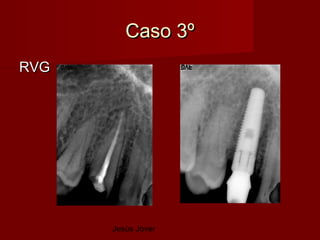

Caso 3º

RVG

Jesús Jover